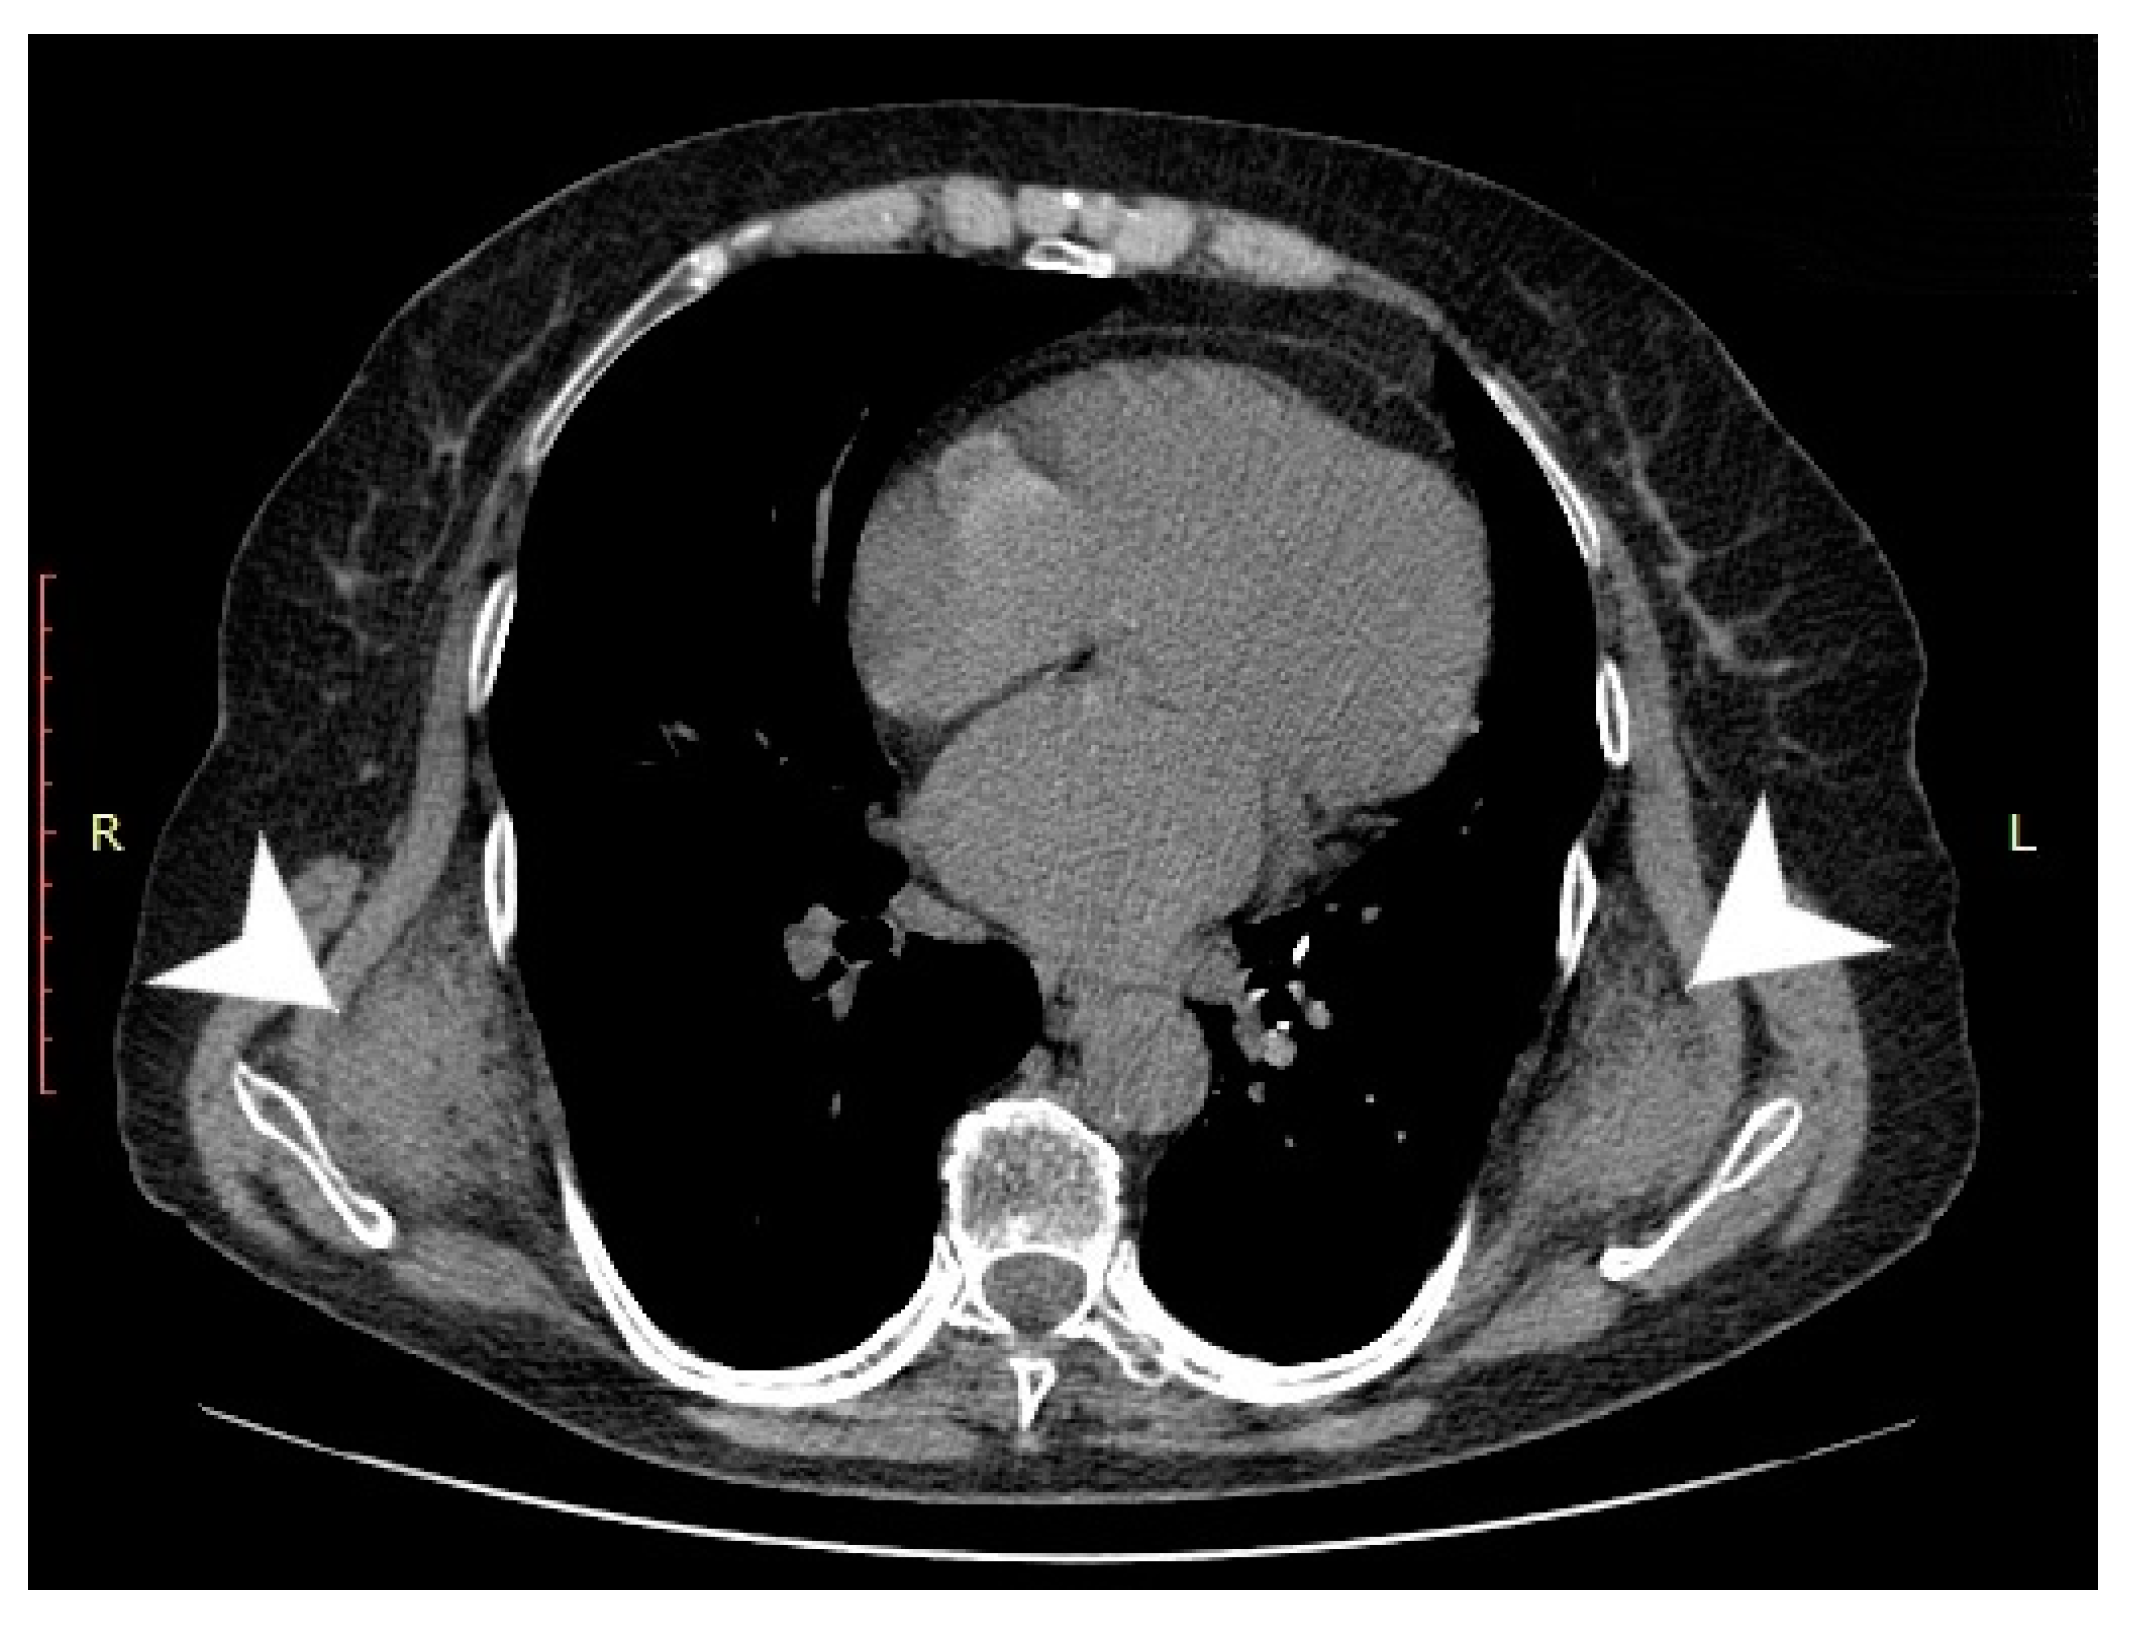

2. Case Presentation